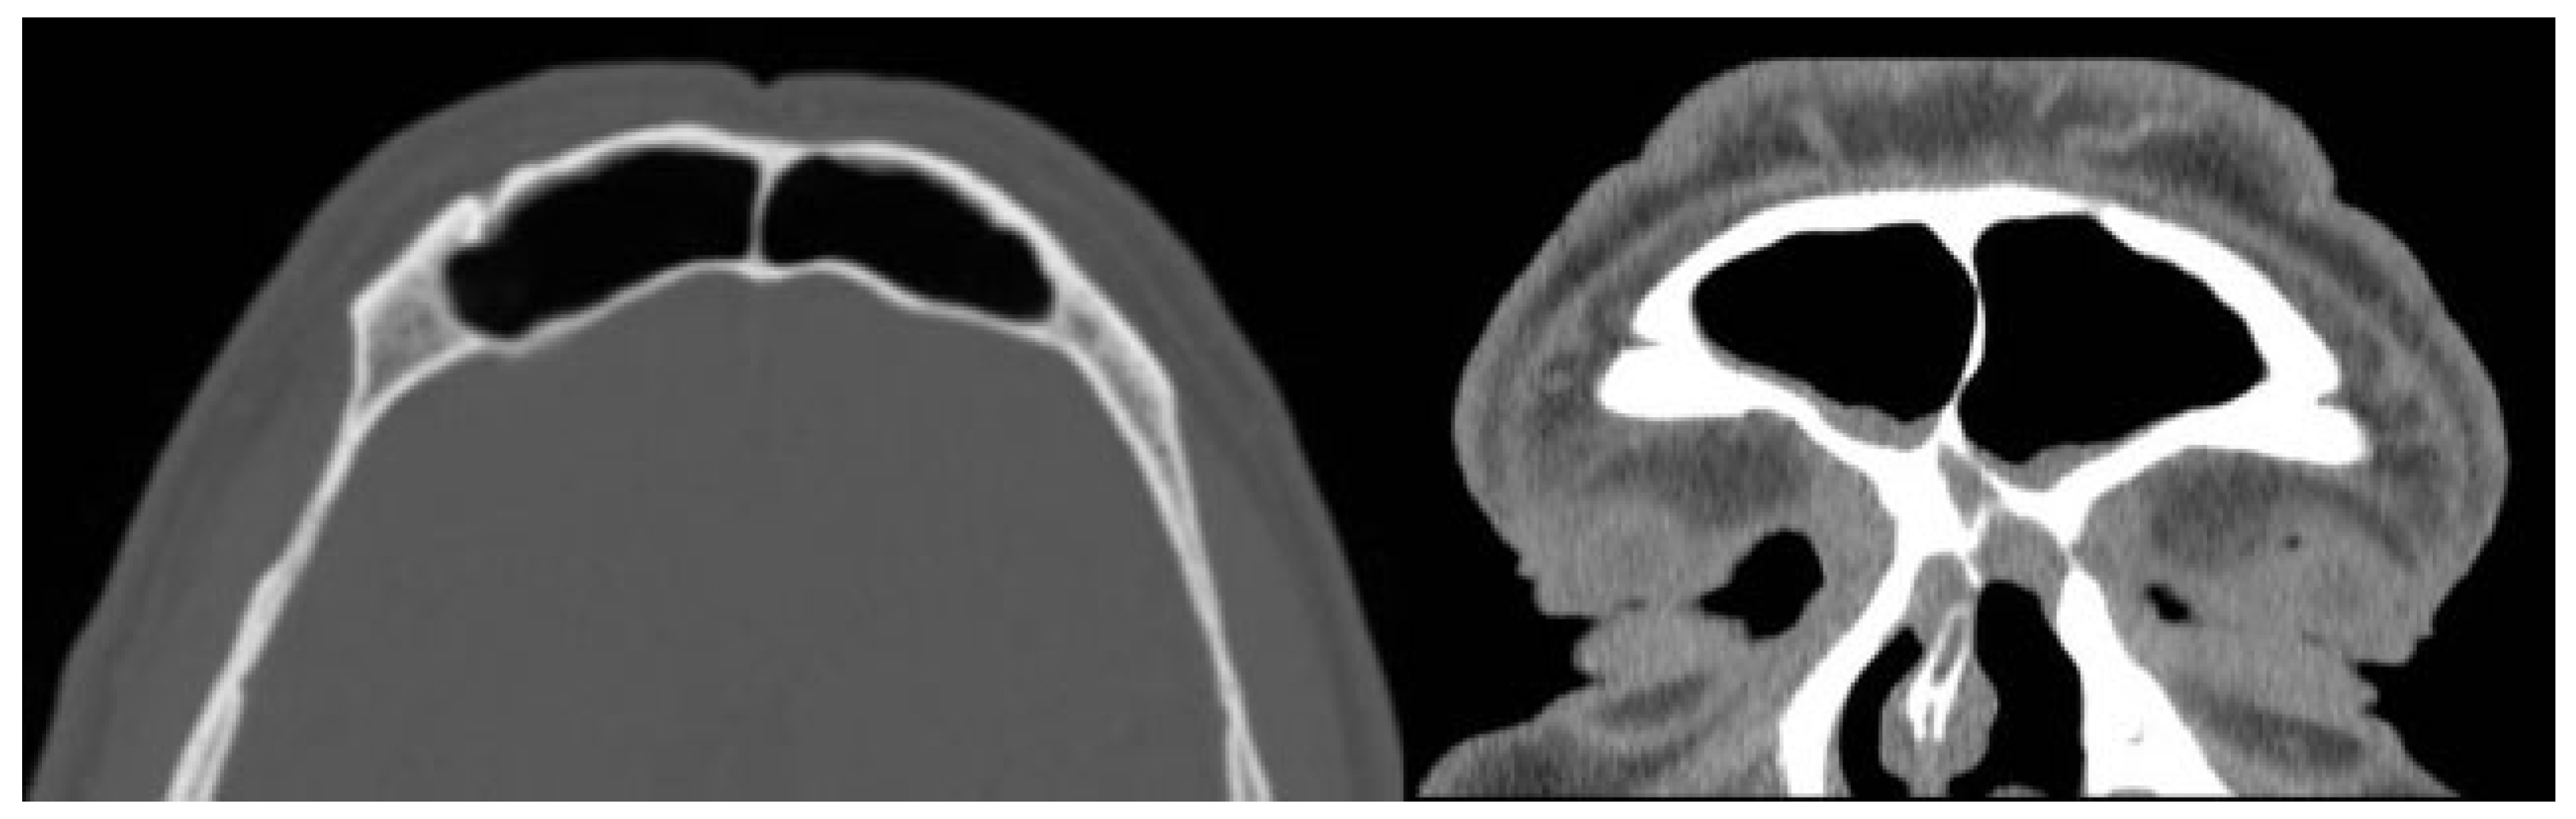

Computed tomography (CT) revealed a wide loss of substance in the root of the nose and a cystic neoformation involving the nasal bones (Figure 2). Magnetic resonance imaging (MRI) showed a globular cystic lesion with a fluid content occupying the upper region of the root of the nose and partially protruding into the nasal cavity (Figure 3). CT scan and MRI showed no involvement of the frontal sinus and frontal recess (Figure 4).

Figure 2. Preoperative CT scan: loss of substance in the root of the nose and cystic neoformation involving the nasal bones.